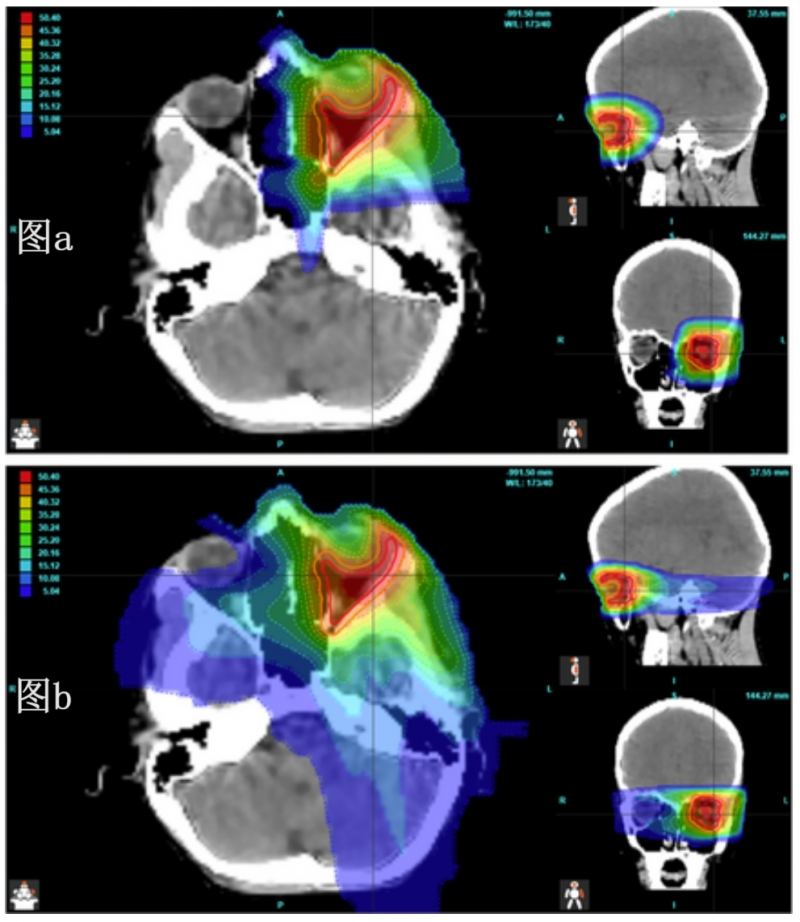

图2 颅咽管瘤病例质子治疗与IMRT(调强放射治疗,一种传统放疗的高端模式)照射剂量对比图

▲图源“BMC”,版权归原作者所有,如无意中侵犯了知识产权,请联系我们删除

注:彩色区域分别代表:右颞叶(黄色)、左颞叶(绿色)、脑干(粉色)、左眼(浅蓝色)、右眼(浅绿色)、交叉(蓝色)。

根据上图,传统放疗辐射剂量波及范围较大,而且需要多个方向同时照射,方可达到杀死癌细胞的目的,对病灶周围健康组织伤害较大,易引起严重副作用。而质子治疗可实现“精准爆破”,辐射波及范围较小,对周围健康组织(如颞叶、双侧视神经、眼眶结构等)伤害较小。